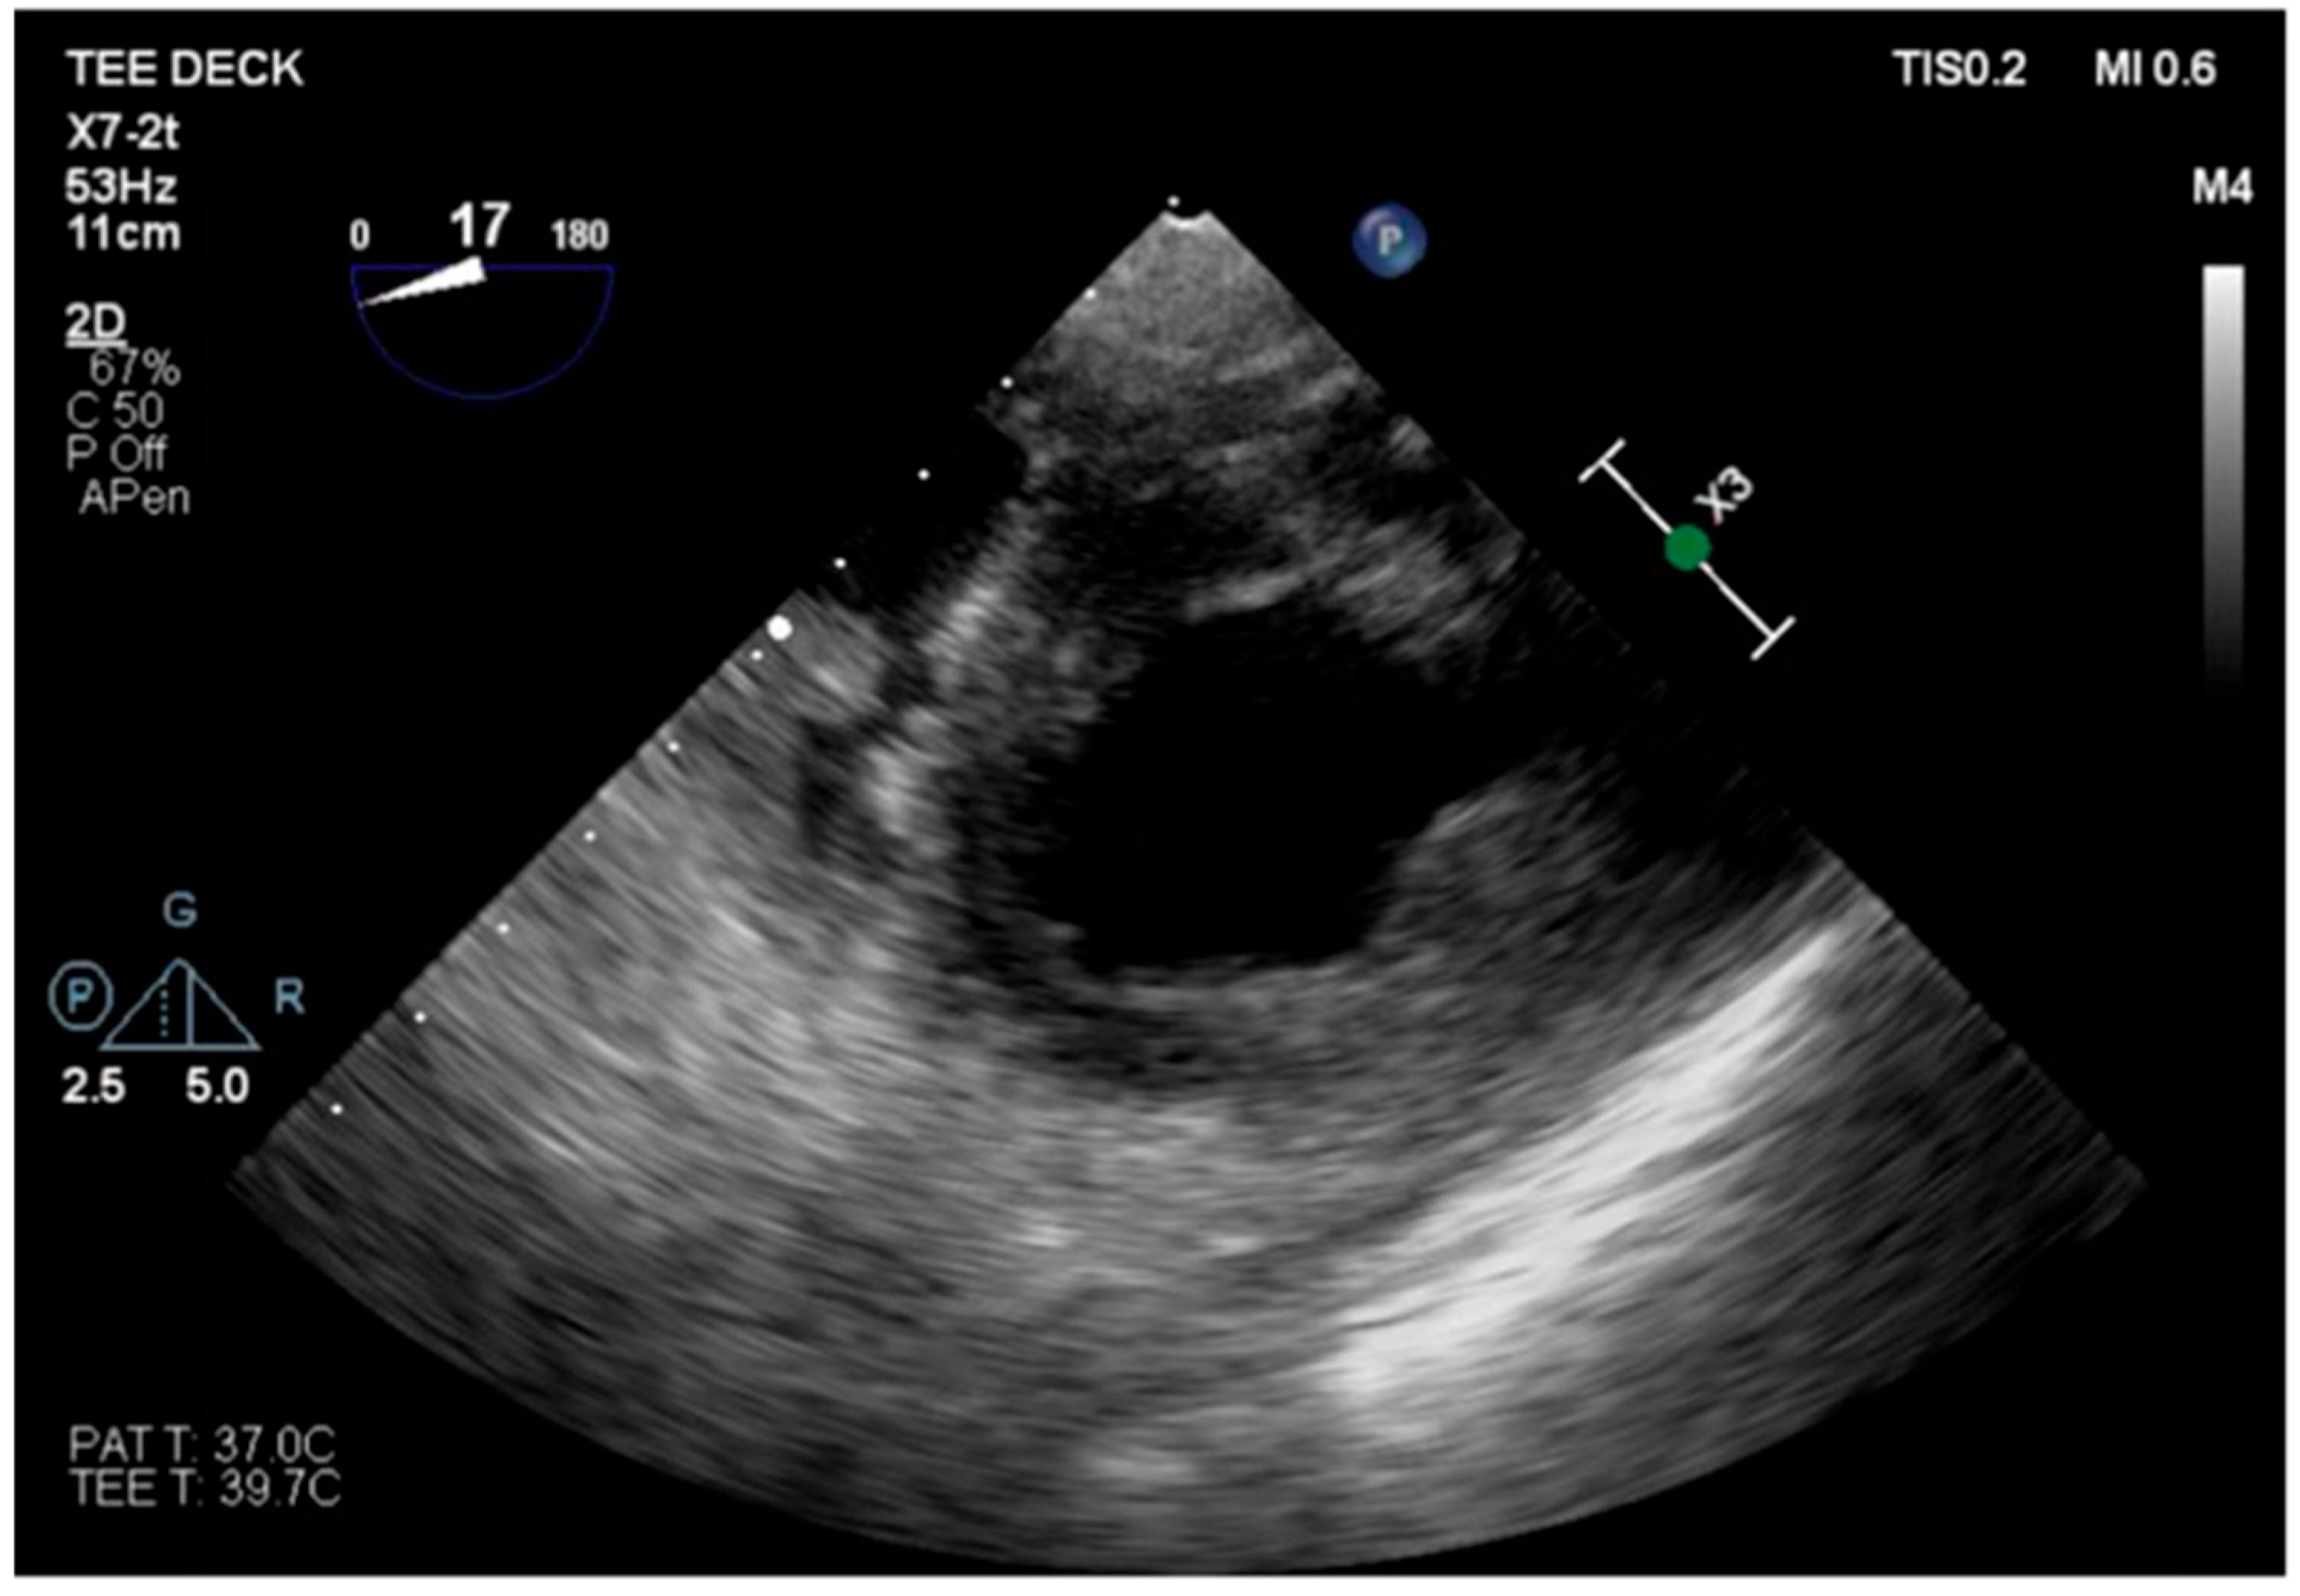

The transesophageal echocardiography showed LVOT-VTI 10 cm; apical, septal, and anterior wall akinesia; preserved function of the medium-basal segments of the inferior and lateral walls (Figure 3, Figure 4 and Figure 5); and RV-FAC 39% with an unloaded right ventricle (Figure 6).

Figure 3. TG mid-papillary level, the day after surgery (T0).